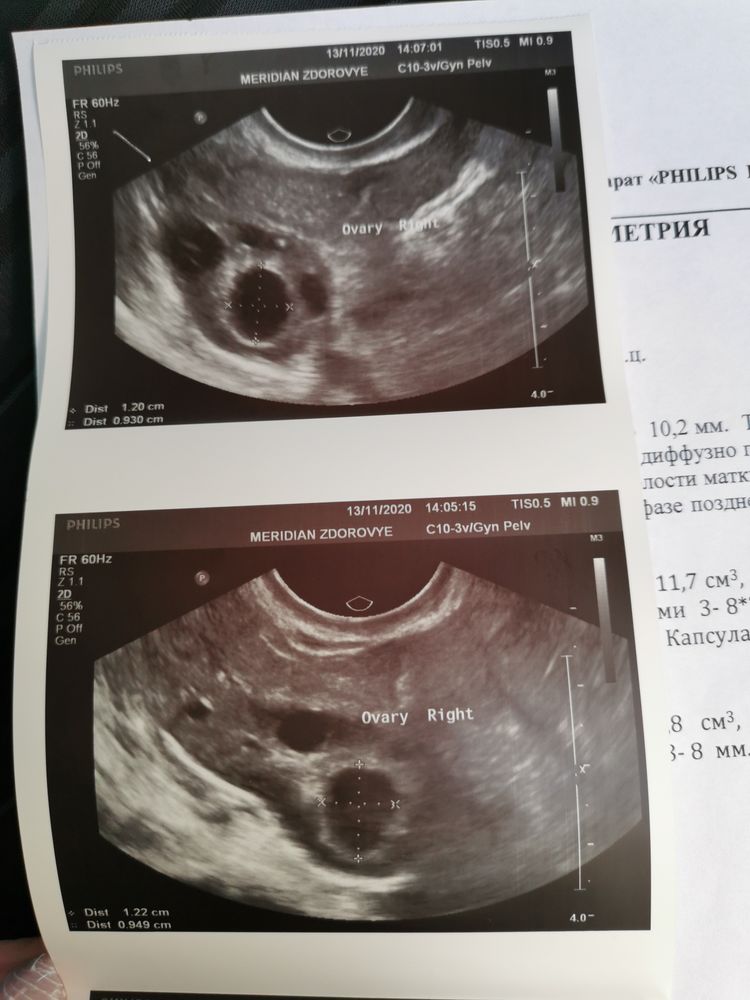

Овуляция( тесты на овуляцию)Девочки, милые) гляньте, пожалуйста, узи. Совулировавший ли фолликул или уже не надеяться? 16дц из 27. С 14 дц на дюф.

12 мм мало, О минимум 18 мм. Вы стали пить дюф в этом месяце можете О не ждать, дюф ее подавит даже если она должна была бы быть. Но я так понимаю у вас нет О, вам нужно разбираться и что-то делать для того чтобы О появилась. По другому никак.

Нет, не совулировал. А зачем тогда Дюф так рано начали? Но успокою - он не остановит О.

Ой, да странная.. Сказала, что мол он 12 мм, и под вопросом персистирующий. И у жт должны быть края не ровные, а тут вроде он ровный. Вроде и есть жидкость, но очень мало, даже не стала вписала в описание 🤷♀️

Нет, не было. Сейчас ставят Мфя. Пью эутирокс и метформин. История такая, по назначению пила кок около 5 лет, для мц и не планировала ещё тогда. Как решили планировать, в результате обследования выяснилось, что 0 своей нет. В прошлом мц могло не быть и по полгода. Назначили дюф для вызова мц, чтобы проверить гормоны. Потом, не дообследовав, как я сейчас понимаю, стали стимулировать клостом одним, безрезультатно. Поставила спкя. Отправила на лапару. Решила проконсультироваться у другого врача. Назначила до обследование. Выяснили что повышенная инсулинорезистентность и высокий ТТГ, назначили эутирокс и метформин, в следующем цикле пришла первая моя О на 11 дц. А в последующем цикле снова не было О, ну и сейчас вот такая картина.